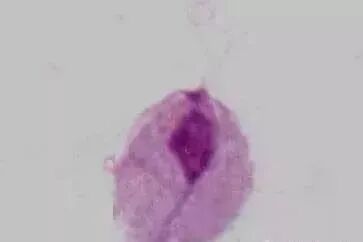

霉菌检查阴道霉菌多为白色念珠菌,诊断以找到霉菌为依据白色念珠菌平时可寄生在阴道内,当阴道内糖原增多,酸度上升时,可迅速繁殖其形态,在生长受抑制环境中,以短杆状存在,而在有利于繁殖的环境中,则变成有丝的霉菌;在这两种形态之间,还有其他形态,故作显微镜检查时,应慎重。

阴道霉菌(白色念珠菌):镜检可以看到较多芽孢和细长的菌丝阴道白色念珠菌感染常见于:糖尿病患者、孕妇、大量使用广谱抗生素或肾上腺皮质激素造成阴道菌群紊乱者此外,维生素B缺乏,免疫机制减弱或使用免疫抑制剂者也可发生阴道白色念珠菌感染。